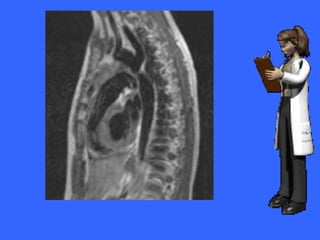

• El crecimiento del VD en los adultos se

aprecia por la disminución del espacio

retroesternal.